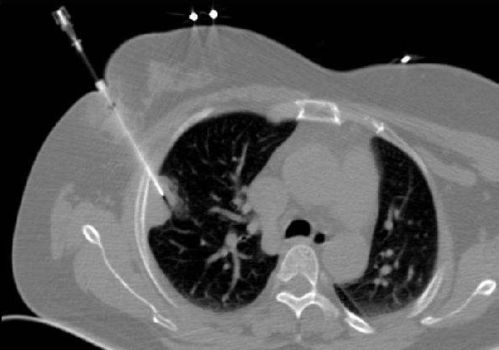

對肺穿刺活檢的目的要明確,不能對疑診血管性病變進行穿刺活檢。對大血管旁病變穿刺活檢要慎重選擇最佳路徑,避免損傷血管。

最主要的并發(fā)癥為肺內(nèi)出血及氣胸,最好在CT引導下進行以提高準確性,由富有操作經(jīng)驗的醫(yī)師來做,可提高成功率及減少并發(fā)癥。手術(shù)中對某些特殊麻醉劑要按使用說明進行(有些要做過敏試驗)。

只是穿刺適用于外周性包塊,離胸壁較近的。最大的副反應(yīng)是氣胸,發(fā)生率較低,且容易處理。